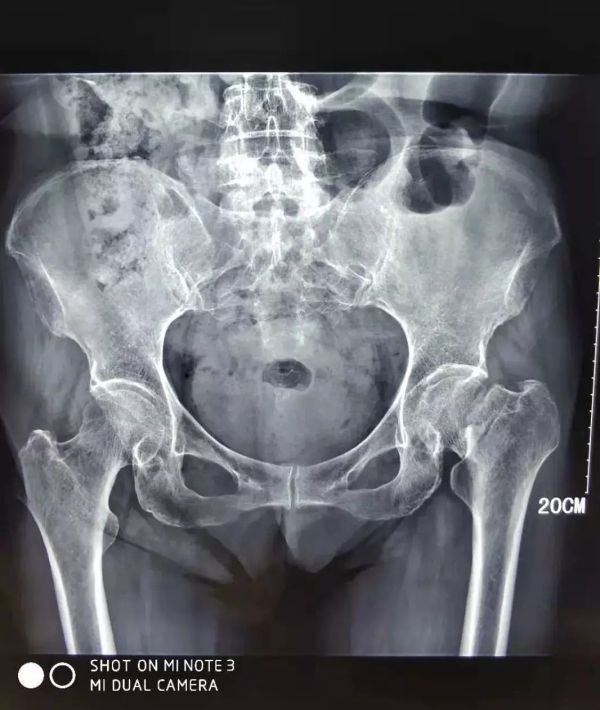

醫(yī)院片子

患者臥床兩個(gè)月后骨折移位更大了